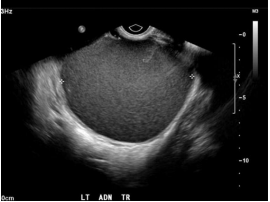

67. 王女士 35 歲,因下腹悶痛至婦科門診檢 查,超音波發現一個 6 公分單側卵巢附屬器官腫瘤 (如右圖),依照圖示特徵最為可能之診斷為何?(A) 黃體囊腫 (Corpus luteum cyst)(B) 卵巢癌 (Ovarian cancer)(C) 畸胎瘤 (Teratoma)(D) 巧克力囊腫 (Chocolate cyst)